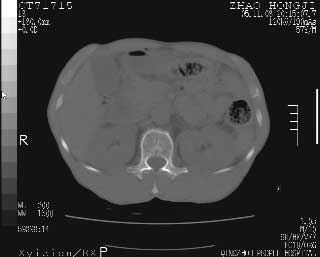

临床资料:男性,57岁,上腹部疼痛并5天,突然加重并延及全腹伴恶心5小时入院。胰淀粉酶化验在正常范围。检查:腹肌紧张,全腹压痛、反跳痛,尤以右上腹部为著。肠鸣音减低。血常规:wbc14.6x10/9, n:11.3x10/9 ,血压:135/90mmhg. 胸部透视:腹部肠腔轻度张气,未见其它异常改变。

肝右前缘少量积气,其他未见明显异常.考虑上消化道穿孔.

小网膜囊积气液,胃壁僵硬。考虑胃穿孔。

小膜网膜积液,肝缘气腹征,上消化道穿孔。

肝缘见少许气体,胰尾部见少许气体包饶(蓝色圈),12指肠上部或球部邻近胆囊周边也可见少许气体影(黄色圈),并忖托出胆囊壁,12指肠远段肠道内未见明显气体(白色箭)。

肝脏前缘见少量积气、胰尾部见少许气体包饶,肾前筋膜未见增厚,临床淀粉酶不高,意见:上消化道穿孔。

消化道穿孔。12指肠球部周和胰周积气考虑12指肠穿孔可能性大。

入院3小时后行剖腹探查术,见腹腔内大量脓性混浊液约1000ml,十二指肠球部溃疡穿孔,溃疡面约2.5x2cm,穿孔直径约0.6cm。胃内容物外益,周围组织炎性水肿明显。行十二指肠穿孔修补术。术后诊断:

1、十二指肠溃疡穿孔

2、弥漫性腹膜炎

对于少量的腹腔游离气体,ct检查较普通透视有绝对的优势,它不仅可以看到肝脏前上缘的气体,而且还能够看到小网膜区的游离气体。从而可以肯定诊断。各位分析战友的很好,感谢大家的参入!